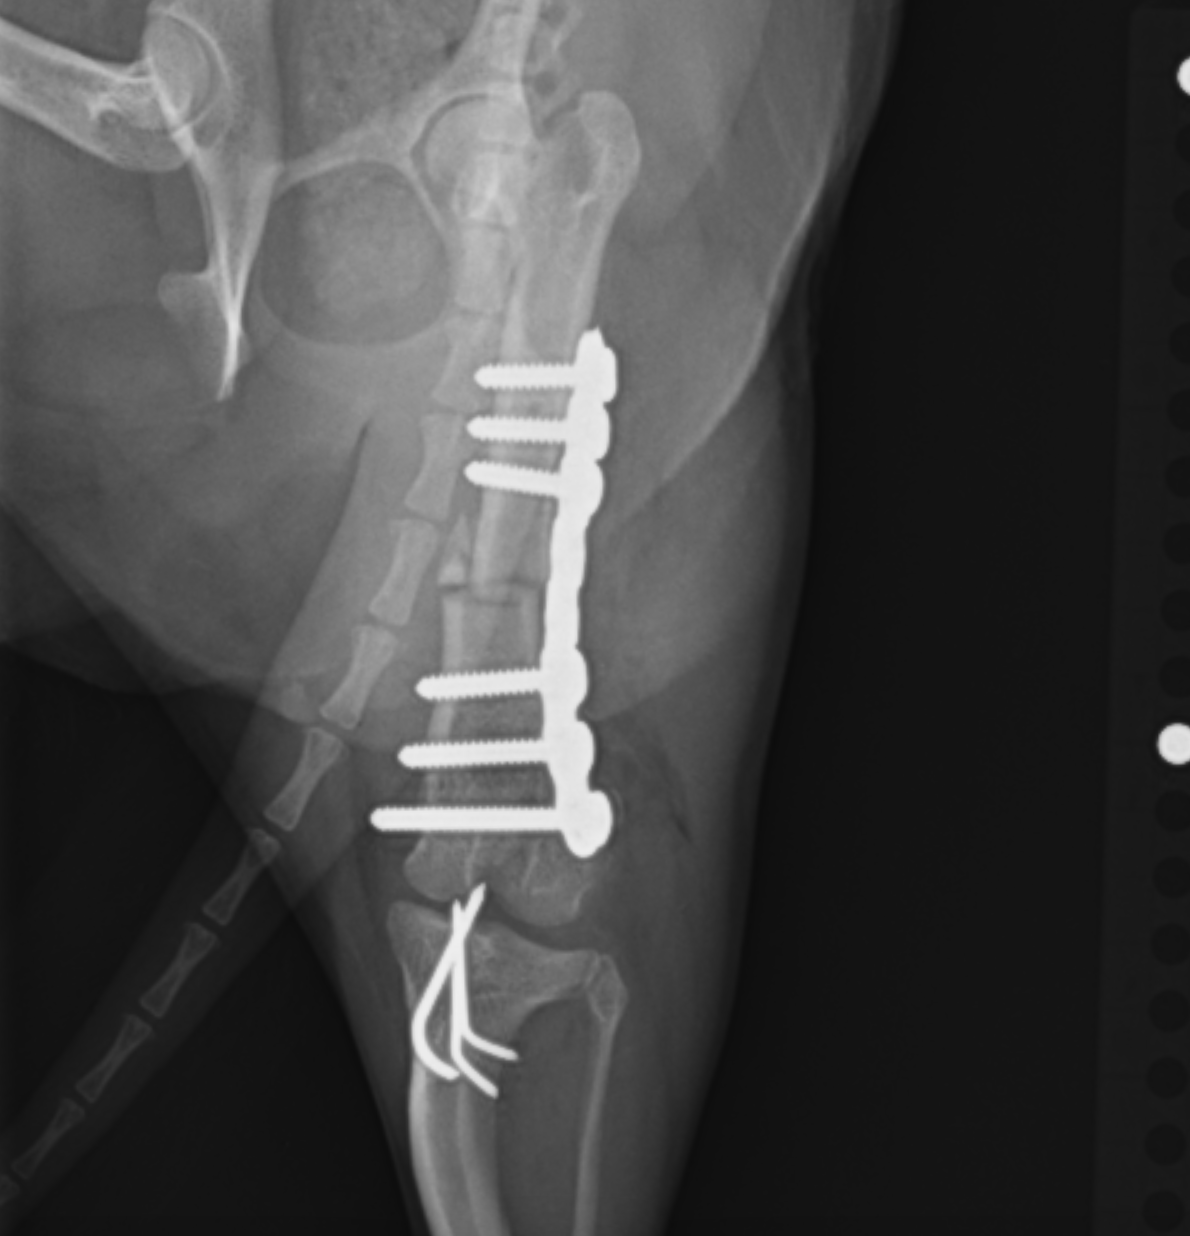

2025年6月22日開催の第110回日本獣医麻酔外科学会学術集会にて磯野がパテラ(膝蓋骨内方脱臼)の形態学的変化についての発表を行いました。CT画像をもとに脛骨の形態学的変化についてご説明させていただきました。

整形外科の雑誌であるVeterinary and Comparative Orthopaedics and Traumatologyに磯野の論文である「Tibial Torsion Malalignment in Small Dogs with Medial Patellar Luxation」が掲載されました。パテラ内方脱臼に対し、脛骨粗面と足根骨の捩れが関与しているをことを示し、その指標の一つを提言した内容になります。ご興味ある方はご覧ください。